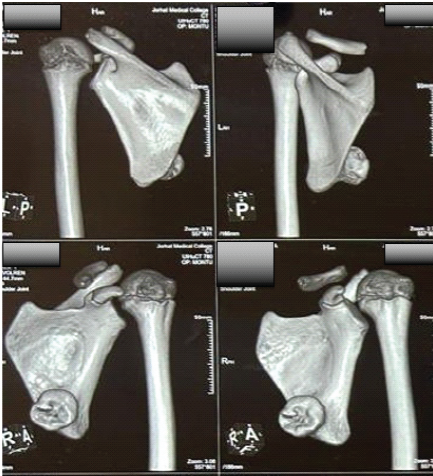

Initial X-rays were suggestive but inconclusive due to the overlapping of the rib cage. Computed tomography of the left scapula demonstrated a well-defined, pedunculated bony lesion arising from the ventromedial surface, with continuity of cortical and medullary bone, consistent with an osteochondroma (Fig. 2). In view of the progressive mechanical symptoms and clear radiological correlation, surgical excision was considered the most appropriate management option.

Figure 2: Computed tomography of ventromedial scapular osteochondroma. Pre-operative computed tomography scan of the left scapula with three-dimensional reconstruction, demonstrating a well-defined pedunculated bony outgrowth arising from the ventromedial surface of the scapula, consistent with osteochondroma, obtained during pre-operative evaluation.